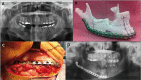

Figure 3

(A) Panorex revealing a mixed multilocular lesion that was approximately 6 x 2 cm in size mainly in the right mandibular body. (B) MRP model created from patient DICOM and its corresponding prebended plate. (C) Submandibular flap with plate and bone graft in place. (D) Postoperative panorex showing correct positioning of the reconstruction plate.